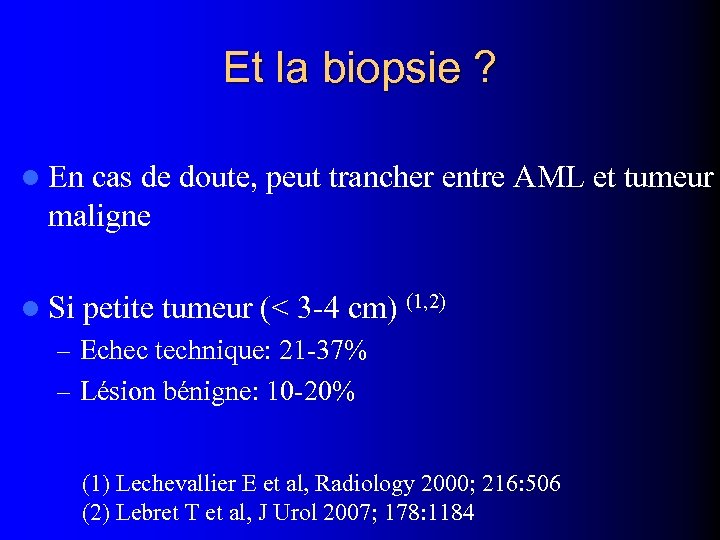

Et la biopsie ? l En cas de doute, peut trancher entre AML et tumeur maligne l Si petite tumeur (< 3 -4 cm) (1, 2) – Echec technique: 21 -37% – Lésion bénigne: 10 -20% (1) Lechevallier E et al, Radiology 2000; 216: 506 (2) Lebret T et al, J Urol 2007; 178: 1184

Et la biopsie ? l En cas de doute, peut trancher entre AML et tumeur maligne l Si petite tumeur (< 3 -4 cm) (1, 2) – Echec technique: 21 -37% – Lésion bénigne: 10 -20% (1) Lechevallier E et al, Radiology 2000; 216: 506 (2) Lebret T et al, J Urol 2007; 178: 1184